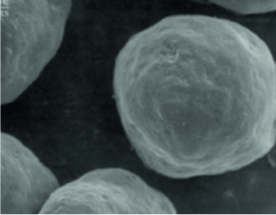

瑞德喜微晶瓷粒子特征与分解

以统一大小和表面光滑的粒子形态可有效对纤维芽细胞起到作用,使ECM(细胞外基质)的再生物质生成达到最优化

(粒子呈尖状或不规则时可能会出现炎症反应)

• radiesse_img14

瑞德喜微晶瓷

(25~45um/Microsphere)

• radiesse_img15

A产品

(30~60um/Crystal)

• radiesse_img16png

B产品

(20~80um/不规则的)